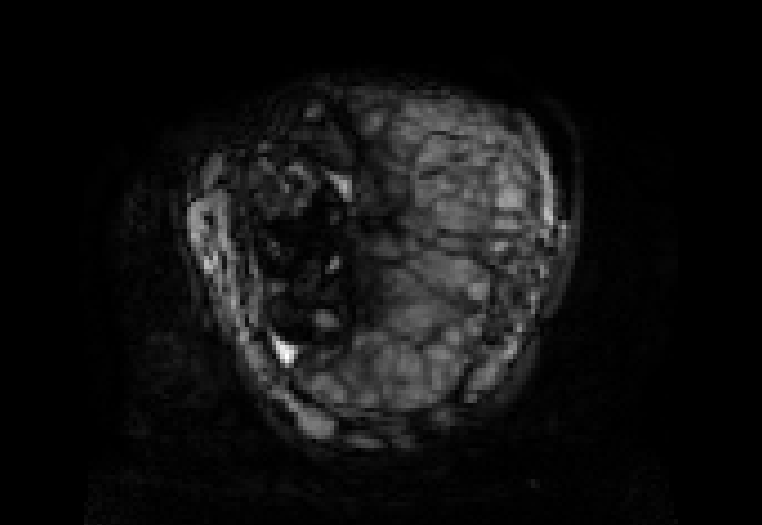

This atlas and the linked publication [1] aim to give a visual overview over T2-weighted anatomical imaging and T2* relaxometry placental data. Both have been widely used in the last years to assess placental structure and function in-vivo [2-10].

Data from healthy controls is displayed over GA, different acquisition choices and possible dynamic effects are depicted and placentae from different cohorts affected by complications are shown.

Display description: All placentae are shown in maternal coronal plane (See A). The slice with the largest placental volume was chosen. The same colormap was chosen for all placentae (See B).